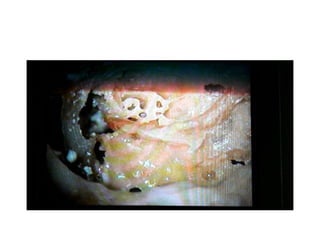

Probing in middle turn

Observe metal probe in perisiers (

dangerous) triangle

Perisiers triangle corresponds to

labyrinthine part of facial nerve

So the metal probe in perisiers triangle goes to the middle turn of cochlea & exactly

corresponds to labyrinthine part of facial nerve So middle turn array of CI stimulates

labyrinthine part of facial nerve causing twitchings in post-op . Then we have to switch

off those electrodes in software programming .